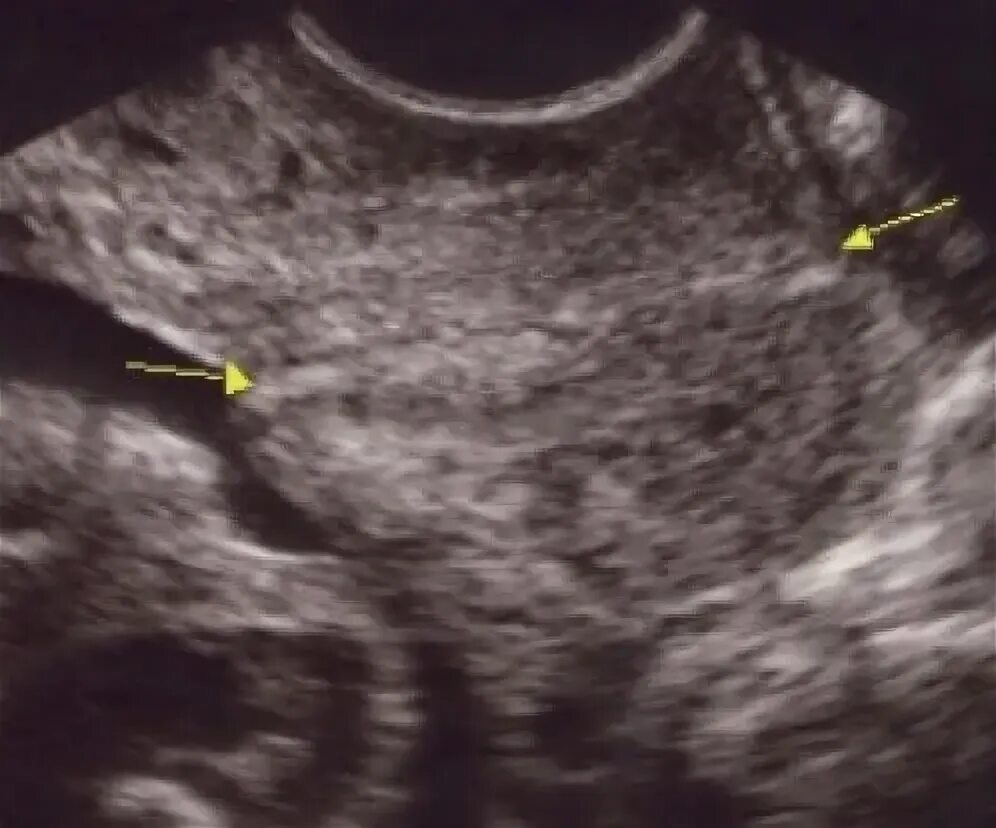

Внутренний зев воронкообразно